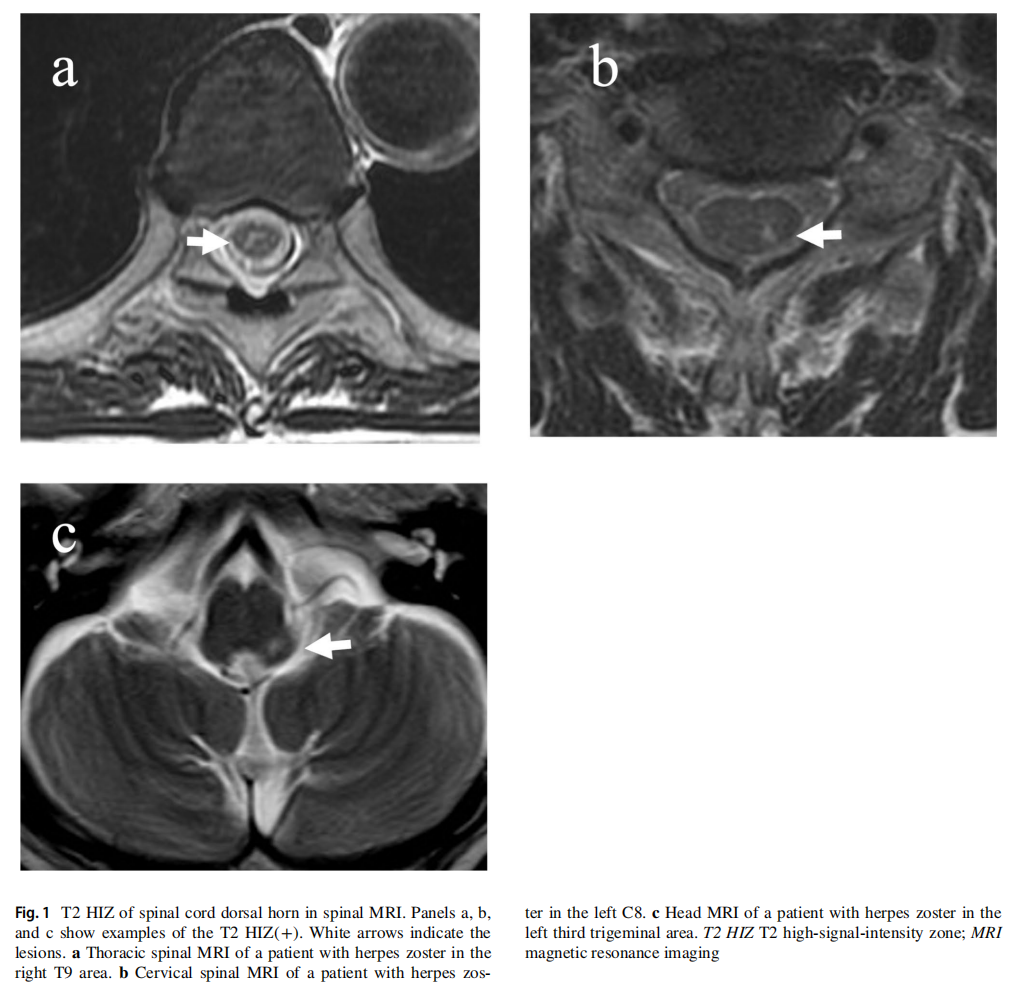

带状疱疹由水痘-带状疱疹病毒重新激活导致,带状疱疹引起的疼痛叫带状疱疹相关疼痛(ZAP)。多数疼痛可自行缓解,部分会成难治性疼痛。按疾病发作后时间,ZAP分三类:发病1个月内为急性,1至3个月是亚急性,3个月以上是慢性疼痛(即带状疱疹后遗神经痛,PHN)。PHN是难治性神经病理性疼痛,10%-50%带状疱疹患者会出现,影响生活质量。 自 2010 年起,该研究团队就开始对保守治疗无效的 ZAP 患者采用 tSCS 治疗。部分患者在 tSCS 治疗前进行脊髓 MRI 检查时,发现 T2 高信号现象(T2 HIZ),且多数发展为 PHN。由此,团队推测 T2 HIZ 可能会影响 tSCS 治疗效果,并且是PHN的危险因素。 此次单中心研究在日本东京 NTT 医疗中心开展,研究过程遵循 STROBE 指南。研究人员从 2010 年 1 月至 2018 年 12 月接受 tSCS 治疗的 ZAP 患者中筛选出符合条件的对象。这些患者需满足带状疱疹发病 6 个月内、2 - 3 种药物镇痛不足、2 - 3 次神经阻滞治疗效果不佳等标准,同时要排除未做脊髓 MRI、发病 91 天后接受 tSCS 等情况。 研究人员重新评估患者的脊髓 MRI 图像,依据脊髓背角是否存在 T2 高信号区域,将患者分为 T2 HIZ(+)和 T2 HIZ(-)两类(图1)。此外,研究还收集了患者的年龄、性别、疼痛程度等背景信息,记录 tSCS 治疗的相关参数,以治疗后的数字评分量表(NRS)评估疗效,NRS≥3 判定为 PHN。 图1

经排除标准筛选后,最终 38 例患者纳入分析(图2),其中 T2 HIZ(+)组 22 例,T2 HIZ(-)组 16 例。两组患者在年龄、性别、首次就诊时 NRS 评分等背景因素上无显著差异。 治疗效果显示,tSCS 治疗后患者 NRS 评分显著改善,总体治疗有效率达 53%。但 T2 HIZ(+)组在治疗后和最终随访时的 NRS 评分明显更高,发展为 PHN 的患者比例也显著高于 T2 HIZ(-)组(68% vs 19%)。这表明,T2 HIZ(+)的患者在 tSCS 治疗后更易残留疼痛,发展为 PHN(图3)。 图2 图3

此次研究首次证实,脊髓 MRI 检查结果不同,tSCS 的治疗效果也存在差异。超过半数的中重度 ZAP 患者脊髓 MRI 出现 T2 高信号区域,该区域很可能是 PHN 的指示指标。若能通过 MRI 检查客观判断 PHN 的发病风险,将为 ZAP 的治疗,如 tSCS 的介入时机和治疗方案的选择,带来重大突破。 不过,该研究也存在局限性。样本量小,难以进行多因素分析;属于回顾性研究,缺乏长期随访和部分患者信息;T2 HIZ 的 MRI 诊断标准尚未确立。未来还需开展前瞻性研究,进一步明确 T2 HIZ 是否为所有带状疱疹患者发生 PHN 的危险因素,探索更有效的治疗方案。